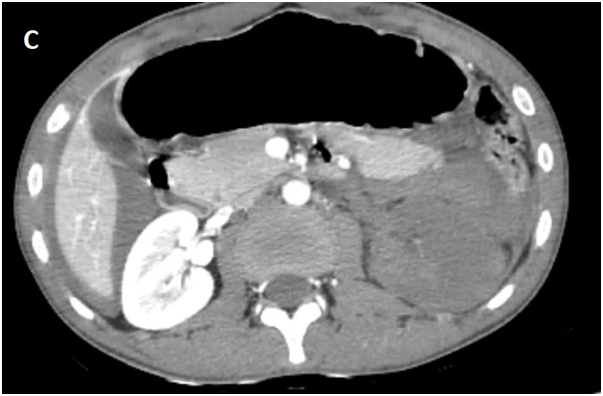

Whole body CT Scanner was performed 5hours after the accident Figure 1, which revealed a laceration fracture of the spleen responsible for a low abundant intraperitoneal hematoma, associated with left renal ischemia due to a sub intimal damage on the left renal artery wall, with formation of a secondary obstructive thrombus, in addition to a left peri-renal hematoma of 16mm, without parenchymal lesions or extravasation of contrast, otherwise ; left vein, the right kidney and his pedicle were intact.

Figure 1A Contrast enhanced CT abdominal scan.

Figure 1B Contrast enhanced CT abdominal scan.

Figure 1C Contrast enhanced CT abdominal scan.

Figure 1D Late acquisition of contrast enhanced CT abdominal scan.

laceration fracture of the spleen responsible for a low abundant intraperitoneal hematoma, associated with left renal ischemia due to a sub intimal damage on the left renal artery wall, with formation of a secondary obstructive thrombus, in addition to a left peri-renal hematoma of 16mm, without parenchymal lesions or extravasation of contrast, otherwise ; left vein, the right kidney and his pedicle were intact.

A Contrast enhanced computed tomography control was performed at D+7 showing a sudden stop of the Contrast progression at the initial portion of the left renal artery, leading to total left renal ischemia, with stability of the perirenal hematoma, spleen injury and no extravasation at the late acquisitions.